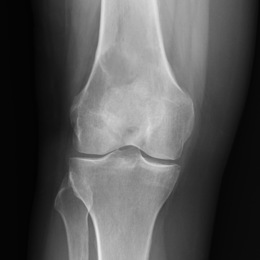

- • More commonly occurs as a soft tissue sarcoma in the muscles of the legs and arms. Most common in the bones around the knee joint, which includes the bottom of the femur and the top of the tibia. The upper part of the humerus near the shoulder is also a common site.

- • The work-up often consists of a physical examination, X-rays, CT scans, MRI, and sometimes bone scans are required. CT scans can be used to check for subtle mineralization that may help with the diagnosis

Radiographic imaging is used to help form a diagnosis. These include X-Ray, MRI, CT and Bone Scans.